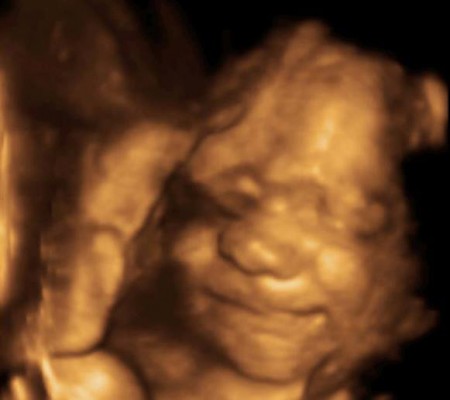

3D i 4D tehnologija omogućava da vidimo površinu bebe na lepši način i pokrete ploda u realnom vremenu.

Takođe nam omogućava da bolje vidimo fetalne mane na licu, šakama i stopalima.

Kao i 2D, 3D i 4D koriste ultrazvučni talas da se kreira slika bebe u materici. 3D je kreirana slika u prostoru dok 4D prikazuje pokret unutar materice pa možemo videti kako se beba smeje, mršti ili zeva.

Za prikaz ovih preseka potrebni su odgovarajući uslovi kao što su položaj ploda (lice ka nama), normalna količina plodove vode, poželjno je da ruke, noge i pupčanik ne budu ispred bebinog lica. U neodgovarajućim uslovima ovaj snimak nije moguće napraviti.

Da bi se dobile dobre slike poželjno je da se pregled radi između 24 i 32 nedelje trudnoće.